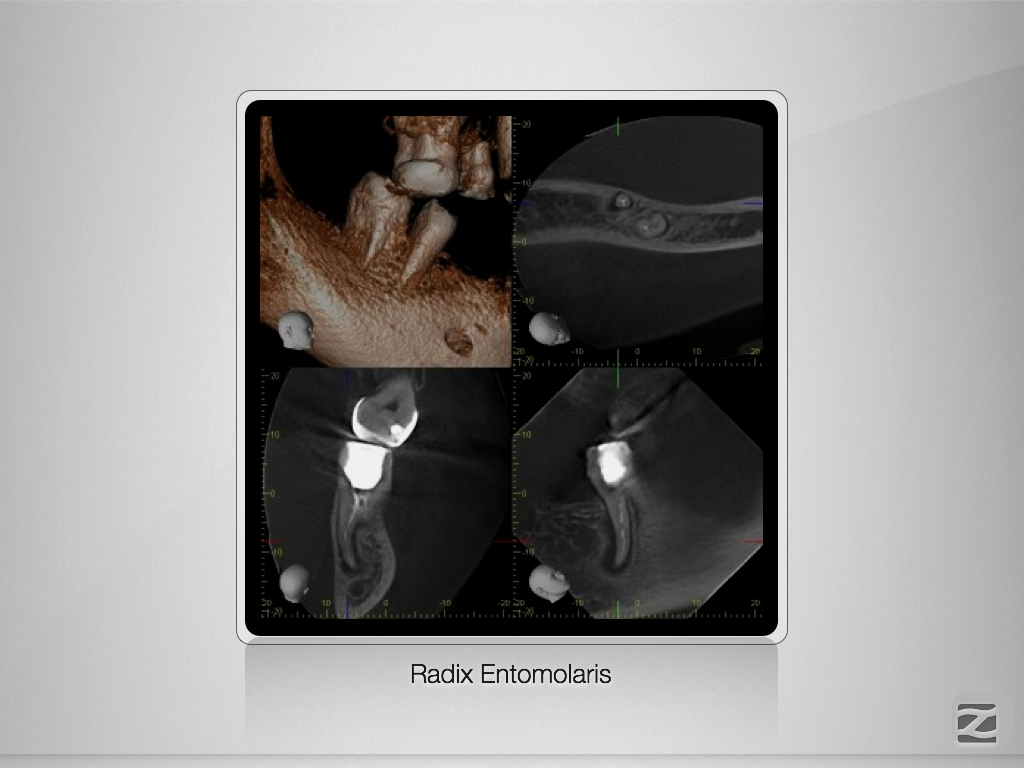

46D.007

Doppeltes C